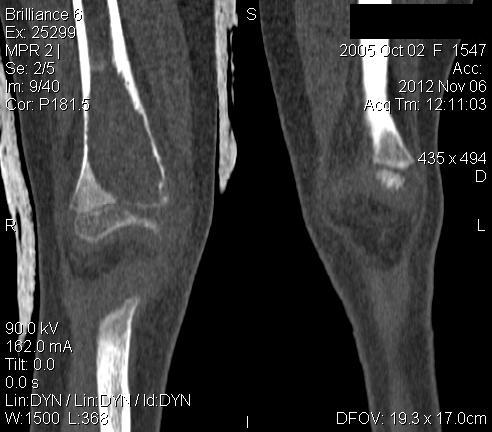

Уважаемые коллеги,

3 месяца назад в отделении была прооперирована девочка 7 лет с

клинико- рентгенологической картиной аневризмальной кисты (открытая

биопсия). Гистологическое заключение местных гистологов и ФНКЦ им. Д.

Рогачева -аневризмальная киста. 2 недели назад девочка взята на костную

пластику - на операции полный лизис костной ткани циркулярно на

протяжении 10 см от эпифиза на 10 проксимальней и массивное

артериовенозное крововтечение из оставшейся надкостницы .

неоднозначна. ФНКЦ им. Д. Рогачева дает прежний результат , ФГБУ РОНЦ НН

Блохина -телеангиэктатическая остеосаркома, онкологи из института

Герцена - киста .Как быть дальше. Кому верить и что делать? Заранее